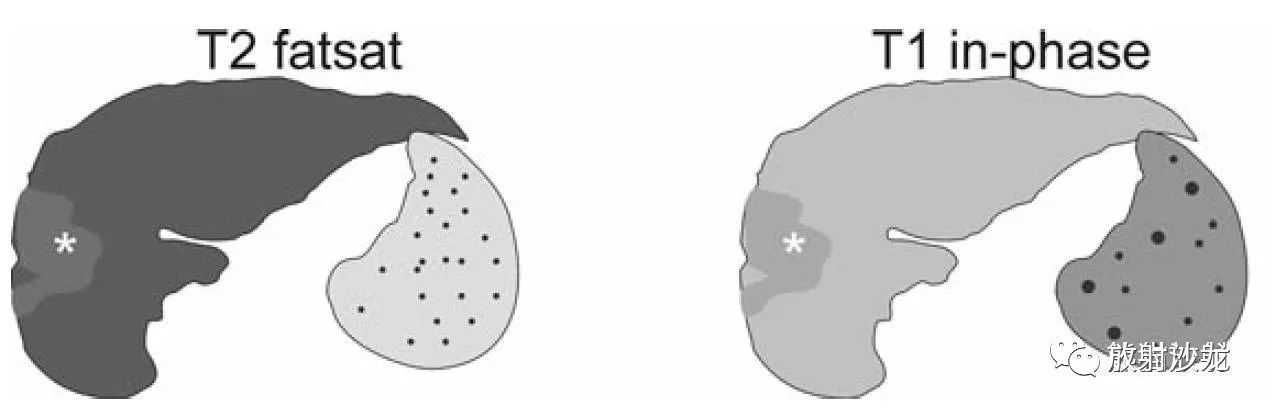

肝硬化,形态示意图:

A、肝左内叶(IV段)萎缩,右叶及左外叶代偿性增大;

B、肝脏萎缩,脾脏增大;

C、肝左内叶(IV段)完全消失,胆囊窝空虚;

D、肝右叶及左叶均增大。